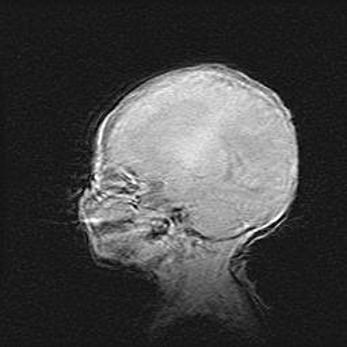

Множественные кисты обоих полушарий головного мозга, наибольшая из них в правой затылочной области. Ассиметричная атрофическая гидроцефалия.

Возраст: 7 месяцев

Вес: 5660 г

Пол: мужской

Окружность головы: 41,5 см

Срок гестации: 28-29 недель

Кисты головного мозга развиваются в результате многоочаговых некрозов вещества мозга и возникают вследствие перенесенной перинатальной инфекции, менингитов, энцефалитов, асфиксии, родовой травмы, расстройств мозгового кровообращения различного генеза. Образованию кист в веществе головного мозга плодов и новорожденных способствуют такие факторы, как высокое содержание в нем воды, недостаточная (или отсутствие) миелинизация и слабая астроглиальная реакция на повреждение.

Кисты могут сочетаться с гидроцефалией и другими поражениями головного мозга.